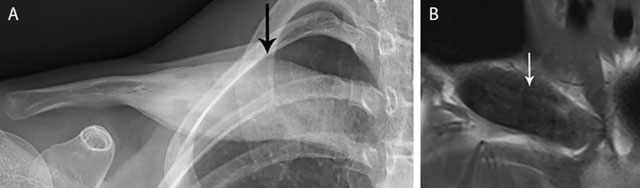

Figure 15

CRMO of the medial clavicle. Plain radiograph (a) shows an expansile lesion (black arrow) of the medial clavicle with extensive bone sclerosis and a solid periosteal reaction. The lesion is of hypo-intense signal on coronal T1–WI (b). Note osseous expansion of the lesion beyond the original cortex of the clavicle (white arrow).